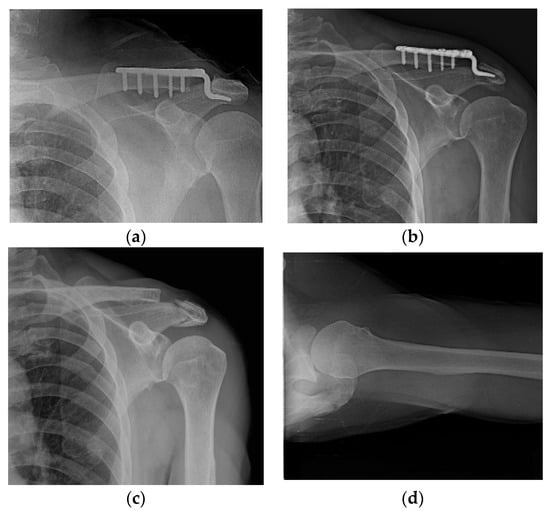

Varying degrees of subacromial erosion occurred in all patients, and acromial fracture occurred in one case in the DCF group and seven cases in the ACD group (Figure 2 and Figure 3). Five (6.7%) cases showed incomplete union and one (1.3%) case showed peri-implant stress fracture in the DCF group (Figure 4 and Figure 5). Four of the five cases of incomplete union showed fracture union without additional surgery during the follow-up period, and one case did not heal at the final follow-up, although the patient did not show any discomfort with non-union (Figure 6). The peri-implant fracture healed with conservative management before plate removal. LOR was observed in nine patients with ACD. Before removing the hook plate, LOR occurred in six patients with ACD. Among these six patients, five showed acromial fracture and one showed serious subacromial erosion (Figure 7). After removing the hook plate, LOR occurred in three patients during the follow-up period. However, none of these patients with LOR among patients with ACD showed tenderness on the acromioclavicular joint or pain during the follow-up period. Regarding acromial fracture, one (1.3%, 1 of 36) case was observed in the DCF group and seven (8.3%, 7 of 33) cases were noted in the ACD group (Figure 4). There was no difference in the incidence of acromial fracture between patients with DCF and ACD (p = 0.066). All eight patients had fracture union without additional surgical treatment during the follow-up period.

Figure 5. Peri-implant fracture. A 76-year-old female patient who underwent AO-type hook plating in the DCF group. (a) Postoperative clavicle anteroposterior radiograph view. (b) Patient showing peri-implant fracture on midshaft area of clavicle during the follow-up period of 4 months. (c) After removing the hook plate during the follow-up period, bone union is achieved.

Figure 7. Loss of reduction in acute acromioclavicular joint dislocation. (a) With severe acromial erosion; (b) with acromial fracture.